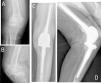

Clinical caseCase 1: An eighty-seven-year-old woman presented to our emergency room with pain, immobility and deformity in her right knee after a low energy trauma. Her past medical history reflected diabetes, hypertension and peripheral vascular disease (Table 1). She lived at home, was independent in basic activities of daily living (BADL) and was able to walk with an assistive device. The patient also had a history of previous knee osteoarthritis. X-ray images (Fig. 1A and B) demonstrated a supraintercondylar femoral fracture (type 33-C3). Hyperglycemia and hypertension were controlled before surgery. Anemia, bleeding disorders and urinary tract infection (UTI) were ruled out. Finally, a primary arthroplasty (DFR) was performed.

Case 1: The duration of the surgery was 75min, and she required two units of blood transfusions. Post-operative X-ray images showed a correct implantation (Fig. 1C and D). Although immediate full-weight bearing was authorized, time until first ambulation was five days (Table 1). Ten days after surgery, the patient was discharged to a residential home. After fifteen months of follow up, she presented good functionality and no complications have appeared. Her Barthel scale score was 65/100 (moderate dependency), her knee range of motion (ROM) was 90° (0–90°) and she was able to walk with an assistive device.